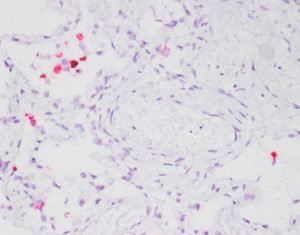

西尼罗河病毒是通过蚊子传播给人类的。虽然高达80%的感染者不会出现症状,但其余20%的人会出现脑炎的典型症状,如发烧、头痛、疲劳、不适、肌肉疼痛和虚弱。当病毒扩散到大脑时,会导致方向感障碍、运动障碍(严重震颤和帕金森病)、瘫痪,甚至昏迷和死亡。

当HIV-1进入大脑时,它靶向小胶质细胞,神经系统的哨兵免疫细胞。感染的小胶质细胞破坏了大脑并引起神经变性(神经元的渐进病)和痴呆。